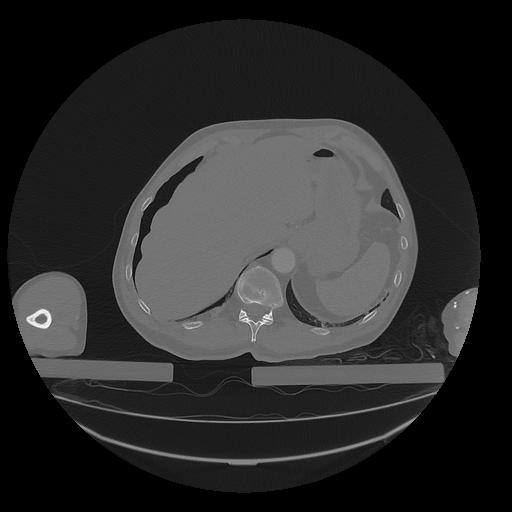

31 PULMON,CE,Vol,1.0,PULMON,,